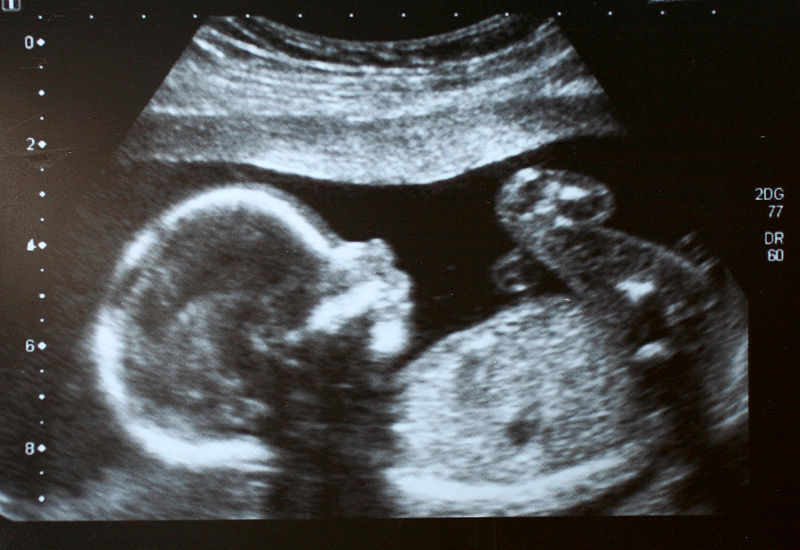

医院的三维彩超、四维彩超、无创DNA、羊水穿刺等都能帮助我们检查出宝宝是否发育正常。

早孕期检查可在10周前或11-14周去做染色体软指标、初步形态学筛查、双胎绒毛膜性判断;中孕期检查可在20-24周做系统性超声筛查;晚孕期检查可在28-34周进行补漏筛查和生长发育检查。